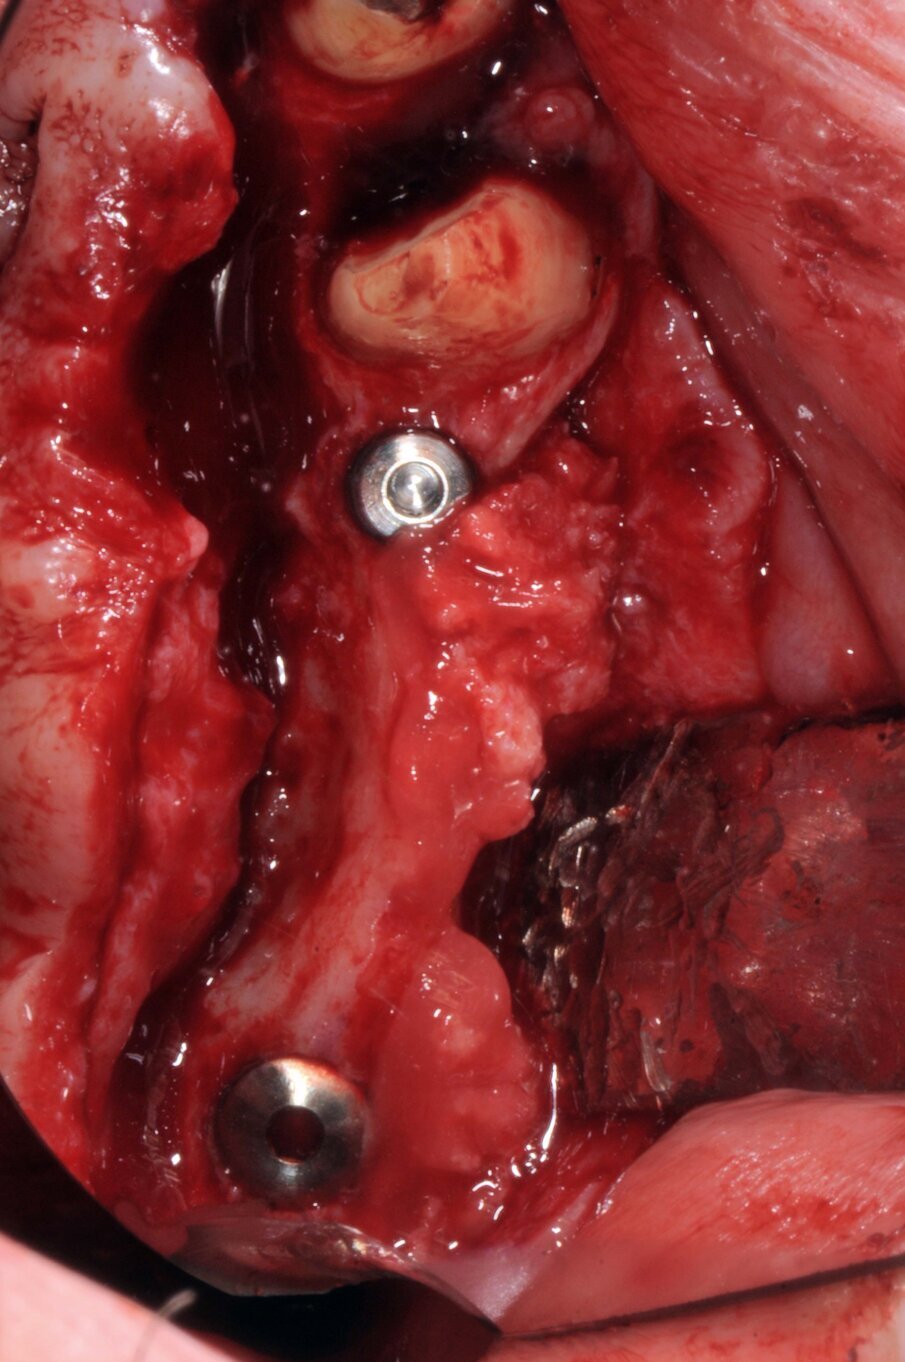

È stato eseguito un lembo a spessore totale senza tagli verticali di rilascio e una regolarizzazione della cresta ossea per mezzo di un raschietto per osso, che ha permesso di ottenere una quantità ulteriore di osso oltre a quello ottenuto per mezzo della fresatura a basso numero di giri secondo la procedura BTI. L’osso ottenuto è stato mischiato con gel piastrinico ottenuto mediante centrifugazione del sangue del paziente secondo la metodica PRGF Endoret ed inserito in parte all’interno dell’osteotomia del dente 26 a protezione della membrana sinusale e in parte protezione della parete ossea vestibolare del dente 24 che era particolarmente sottile. Dopo aver applicato i tappi di guarigione i lembi sono stati suturati per ottenere una guarigione sommersa (Figg. 5-7). Dopo quattro mesi di guarigione gli impianti furono scoperti e due pilastri Multi-im sono stati avvitati con i relativi tappi di guarigione.